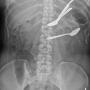

Foreign bodies in the stomach and transverse colon on abdominal X-ray

Case Report Page 834 - 837

Successful Conservative Management of Multiple Spoons Ingestion in a Psychiatric Patient - An Unusual Case Report